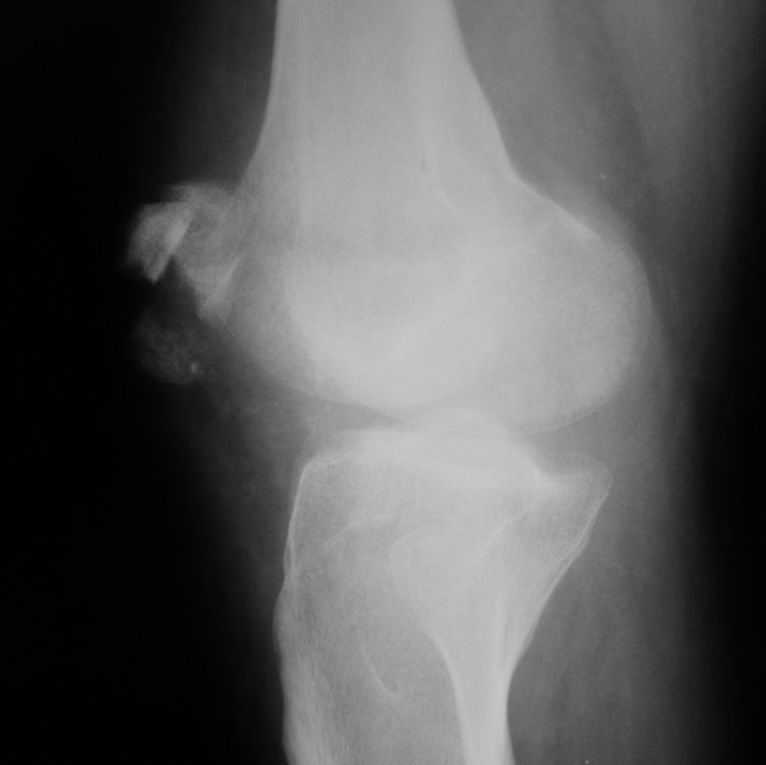

Уважаемые коллеги! Обратился пациент 32 лет с травмой коленного сустава от июля 2008 года - падение с мотоцикла, прямой удар передней поверхностью коленного сустава. Диагноз - открытый оскольчатый перелом надколенника. В одной из больниц города выполнили ПХО, шов надколенника лавсаном. Заживление раны с частичным нагноением(разведена на участке 3 см).Сейчас мягкие ткани в порядке. R-снимки, КТ в приложении. Объем движений 0/0/110 гр.Ходит почти без хромоты. Жалобы на торчащий под кожей один из отломков, боль в этой точке. Вопрос: что делать? Первое - убрать этот отломок и на этом закончить. Второе - оставить все как есть(отломок не так уж и сильно мешает). Ждать возможного развития артроза, дальше по ситуации. Третье - подумать о протезировании надколенника.

Внешний вид коленного сустава